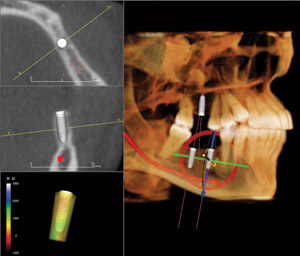

The 3D view dramatically increases acceptance of implant therapy. In the past, the first time that I would present treatment to patients, they would need time to try to understand the concept. Only 25–30 percent made a decision for treatment on the first visit. These days, we are experiencing about a 60 percent acceptance rate on the initial visit, and a 75 percent overall. Why? We are able to show patients their own case in exact 3-dimensional images with implants in place. Prior to 3D, we relied on photos of other completed cases (and their imagination) to describe their procedure and outcome. Now, we are able to show each patient their own case, non-distorted, and in three dimensions. The Anatomage Invivo5 software shows the exact implant location. This creates a clear understanding of the procedure and its benefits to the patient.

The following case illustrates the benefit of CBCT. We were the third opinion on a possible implant case for a 19-year-old who lost all of his lower teeth and sustained multiple mandibular fractures due to trauma. He had also lost much of his alveolar bone. The first dentist suggested implants and a removable appliance. The second dentist told them that an implant-supported fixed appliance was possible. We were the first to take a CBCT scan, which the patient had never seen, that showed a horizontal void in the symphysis area that had gone undetected by 2D radiography.